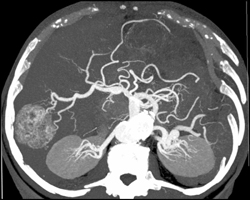

Hepatoma